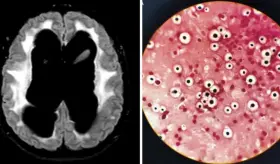

Su diagnóstico comienza de manera incidental, cuando se realiza una resonancia magnética cerebral por otros motivos médicos y se identifica la presencia de la lesión.